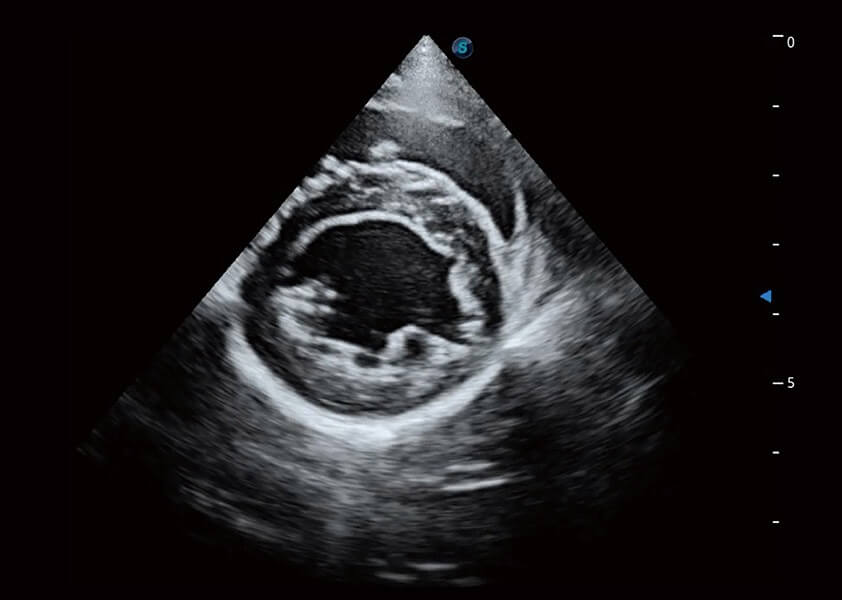

ProPet 60 作为一款高端台式动物超声设备,为动物医生的日常诊断提供了一系列贴合动物临床需求、解决临床实际问题的高级成像功能。凭借全系列高清探头,满足医生对腹部、心脏、生殖、浅表、肌骨等成像的所有需求,切实帮助您提升检查效率,提高诊断信心。

兽用彩色多普勒超声诊断系统

动物是人类最亲密的朋友和最值得信赖的伙伴。milan米兰也一直致力于探索动物专用的超声影像解决方案。 全新推出的ProPet系列,是milan米兰在动物超声影像智能化、专业化、精准化的一次跨越式革新。动物不能用言语来表述自己的不适,通过超声影像,ProPet系列搭建了动物医生与不同物种沟通的“桥梁”,为动物医生注入了“治愈之力”。